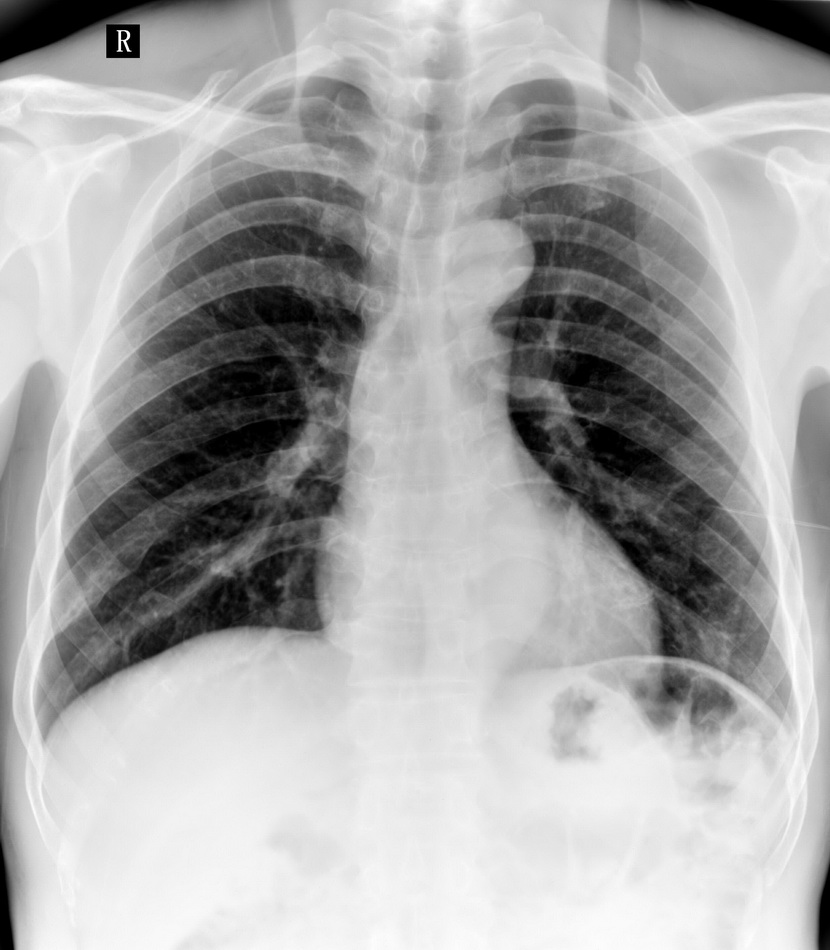

患者,男性,41y,外伤病号,来拍片,发现右侧第9后肋,肋骨膨大,有密度不均,想问大家,是否有问题,要考虑什么东西,谢谢

右侧第九后肋骨纤维结构不良。

考虑骨纤维异常增殖症(混合型)。

肋骨是骨纤好发部位。